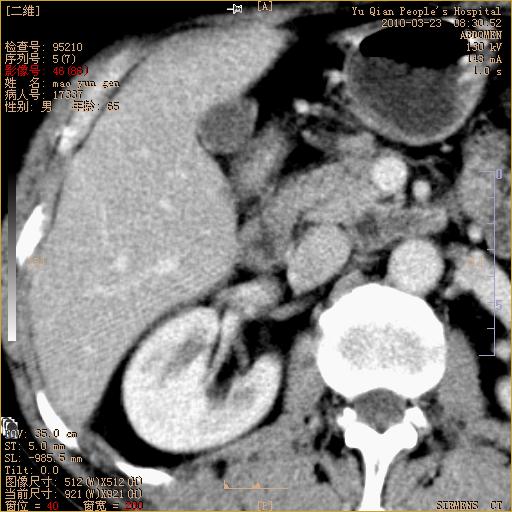

标题: CT25266:消瘦月余,前来肝部检查,请看看肠腔 [打印本页]

标题: CT25266:消瘦月余,前来肝部检查,请看看肠腔

肝区结肠占位,腺癌可考虑,建议肠镜活检。

升结肠肠壁增厚,不均强化,考虑升结肠腺癌可能性,建议肠镜检查。

1)考虑升结肠癌。2)右肾小囊肿。